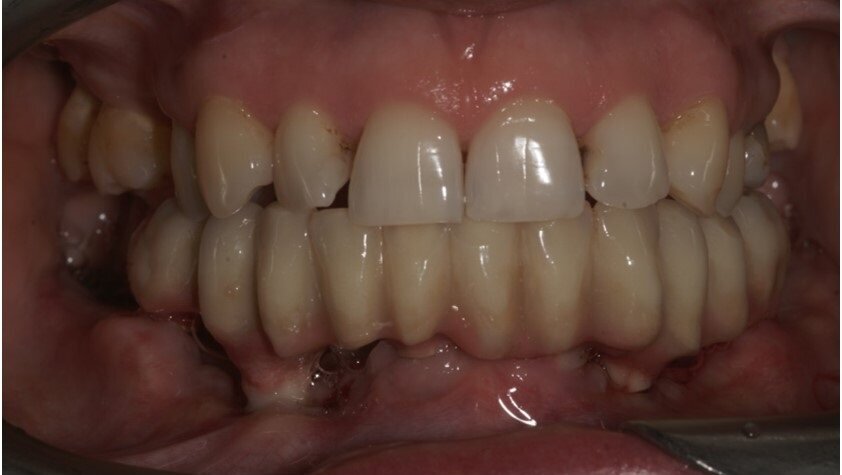

przygotowanej wcześniej protezie czasowej metodą bezpośrednią. Czasowe uzupełnienie protetyczne osadzono, używając cementu tymczasowego (Ryc. 5 i 6). Zlecono wykonanie zdjęcia techniką CBCT (Ryc. 7). Wizytę kontrolną wyznaczono następnego dnia, a szwy zostały usunięte po 10 dniach.

Po upływie 3 miesięcy czasowe uzupełnienie protetyczne (Ryc. 8) zostało wymienione na cementowaną pracę ostateczną (Ryc. 9),